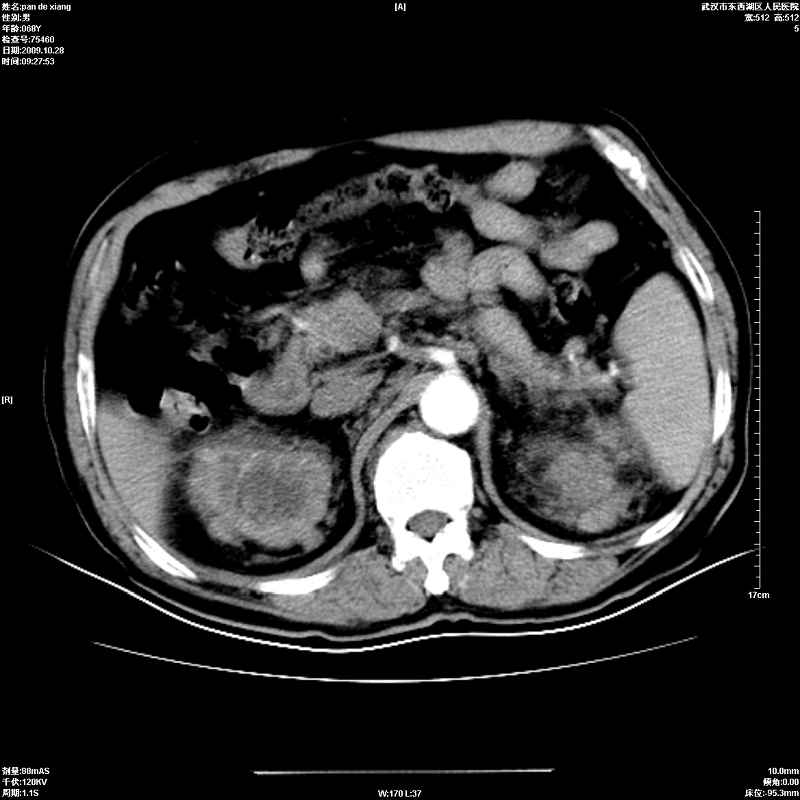

以下是引用杀毒软件在2009-10-28 20:41:00的发言:[br]结合临床考虑---白血病双肾改变或淋巴瘤。

以下是引用zxl51642在2009-10-29 9:59:00的发言:[br]结合临床“单克隆免疫球蛋白血症”,考虑双肾为继发损害并肾功能不全(尿中大量igg及少量iga、igm等大分子免疫球蛋白滤出所致继发损害),椎前软组织肿块为髓外造血。与浆细胞瘤有区别,平扫时有战友说的很清楚。